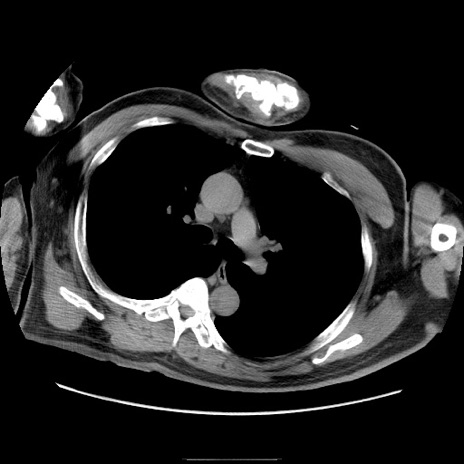

冠状断像

【症例】50歳代男性

【主訴】腹痛

【現病歴】AVMからの被殻出血のため回復期リハ病棟入院中。 本日午後3時頃急に下腹部痛が出現した。

【既往歴】AVM、被殻出血、虫垂炎、高血圧

【身体所見】意識晴明、左半身不全麻痺、会話の理解は良好、36.5°C、腹部:膨隆、全体に板状硬、下腹部正中に圧痛点あり、反跳痛-、筋性防御不明、右下腹部にope scar

【データ】WBC 9400、CRP 0.06